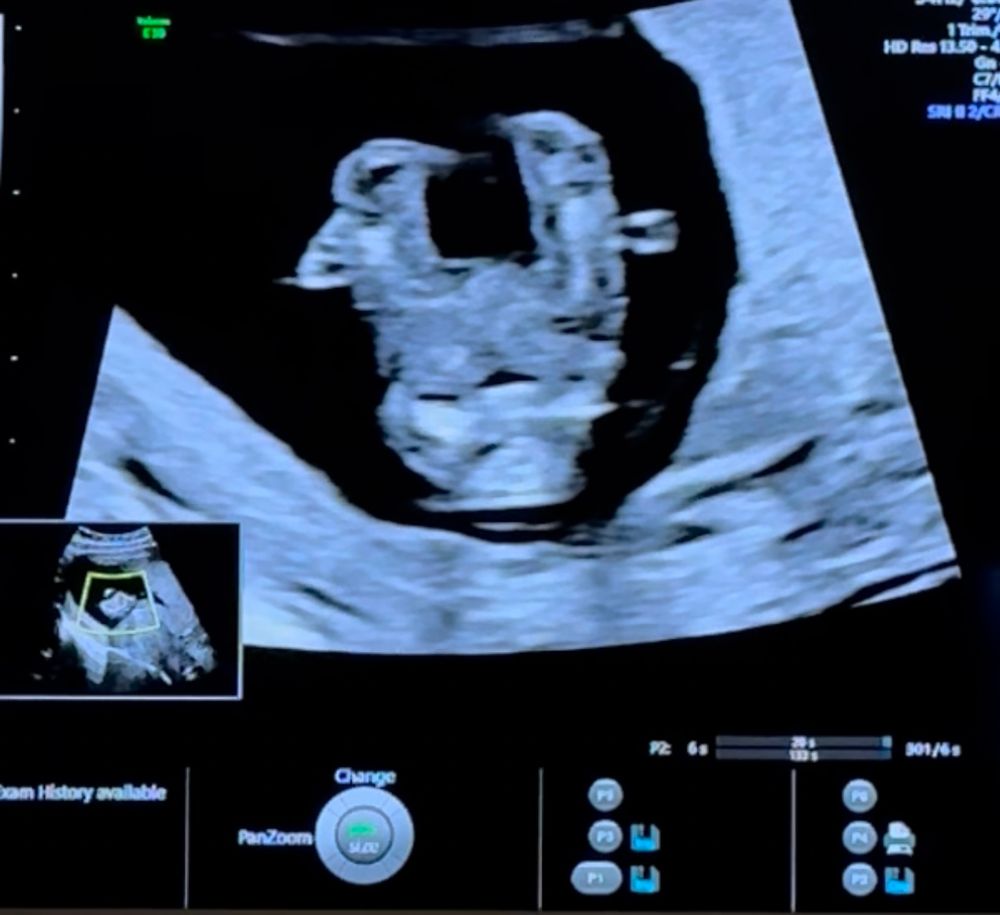

Пол ребенка в 12 недель (половой бугорок), мальчик или девочка?

за ножкой не видно бугорка(

Так не видно же.

Вроде как на девочку похоже, у мальчиков бугорок "крючёчком" вверх

Сбоку ножкой закрылся, а снизу на таком сроке не смотрят ☺️